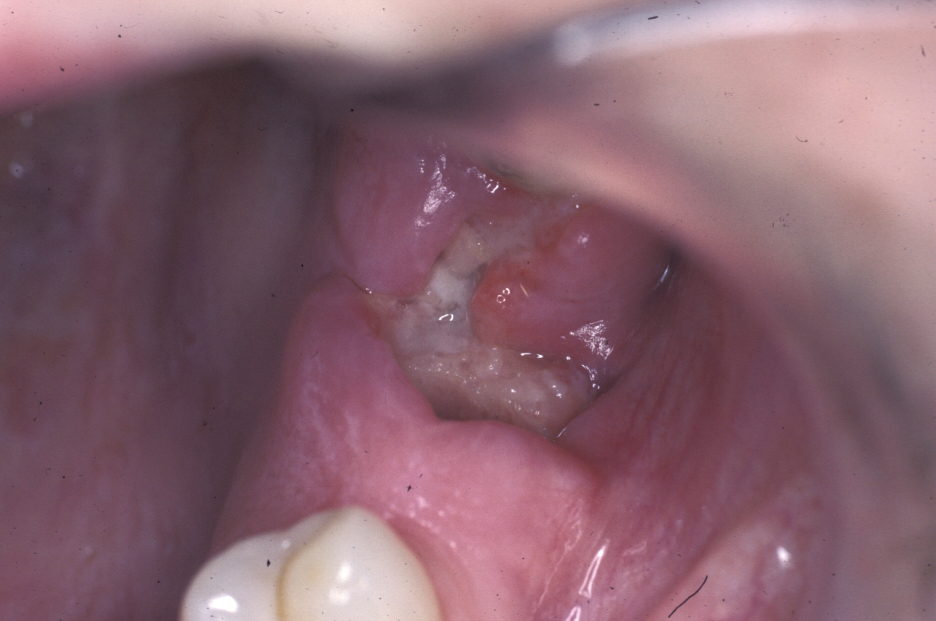

Unicystic ameloblastoma is a cystic swelling distinguished by resorbing adjacent tooth roots: histologically the lesion is an ameloblastoma but it has predominantly fluid contents. Figure 4 shows an example.

Figure 6: Unicystic amelobastoma resorbing tooth roots.

Follicular/plexiform ameloblastoma is a solid tumour, again found in the mandible. It is more aggressive in its clinical behaviour and resembles a solid tumour histologically (see Figure 5).

Figure 7: Sectional dental panoramic tomogram of the ‘soap bubble’ appearance of the solid variety of ameloblastoma.